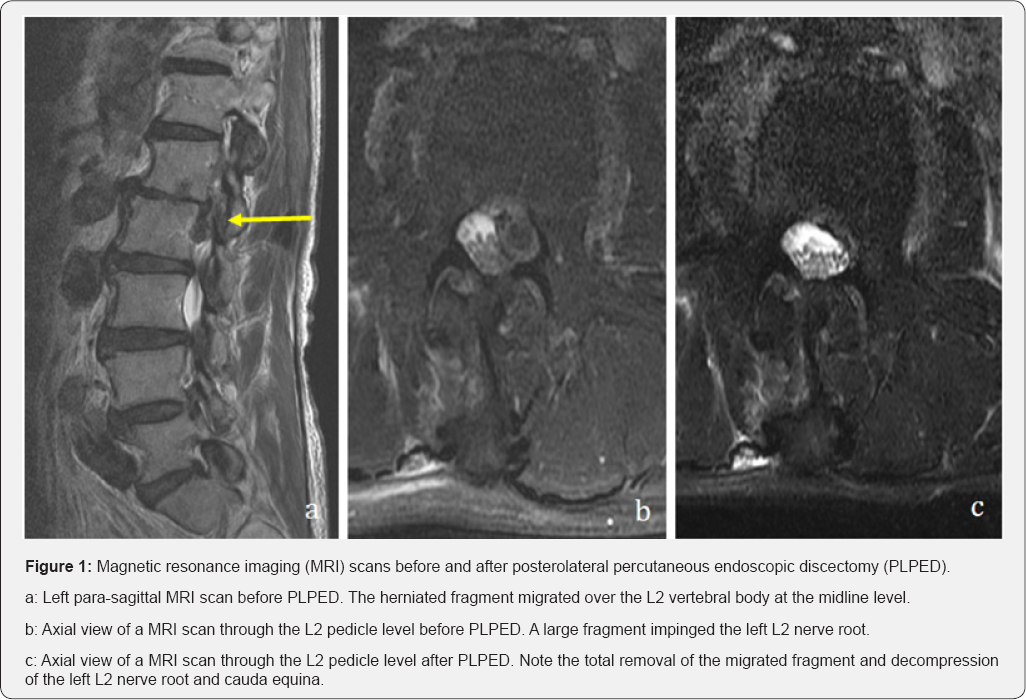

On sagittal T2-weighted magnetic resonance imaging (MRI),a high-grade downward migrated disc was observed at the L1-L2 level on the left side (Figure 1a). The axial view at the L2 pedicle midline level showed a large fragment impinging the L2 nerve root (Figure 1b).

The patient did not have any dysesthesia and paresis. The time to ambulation was 2 hours, and his hospital stay was 7 days. The NRS score of his affected leg improved from 8 to 1 after 2 months. In the next morning, his wound pain NRS score was 1. The axial view of the MRI scan (Figure 1c) showed that the migrated fragment was completely removed.

The major difference between ILPED and PLPED with partial pediculotomy is the direction of the operative approaches. ILPED accesses from dorsal side of vertebral laminae, thereby even combined with laminectomy the migrated fragment is still covered with neural structures. On the other hand, PLPED with partial pediculotomy can directly expose the migrated fragment covering neural structures. In other words, as the migrated fragment protects underneath neural structures, we can safely drill the inner cortical bone layer of the pedicle. Additionally, the width of spinal canal at high vertebral level (ex. L1-L2) is narrower than that at low vertebral level (ex. L5-S1) (13). Consequently ILPED at high vertebral level requires more skillful technic. Our case was affected at L1-L2 vertebral level and the migrated fragment extended lateral part of the spinal canal (Figure 1b), we therefore planned to perform the PLPED with partial pediculotomy.